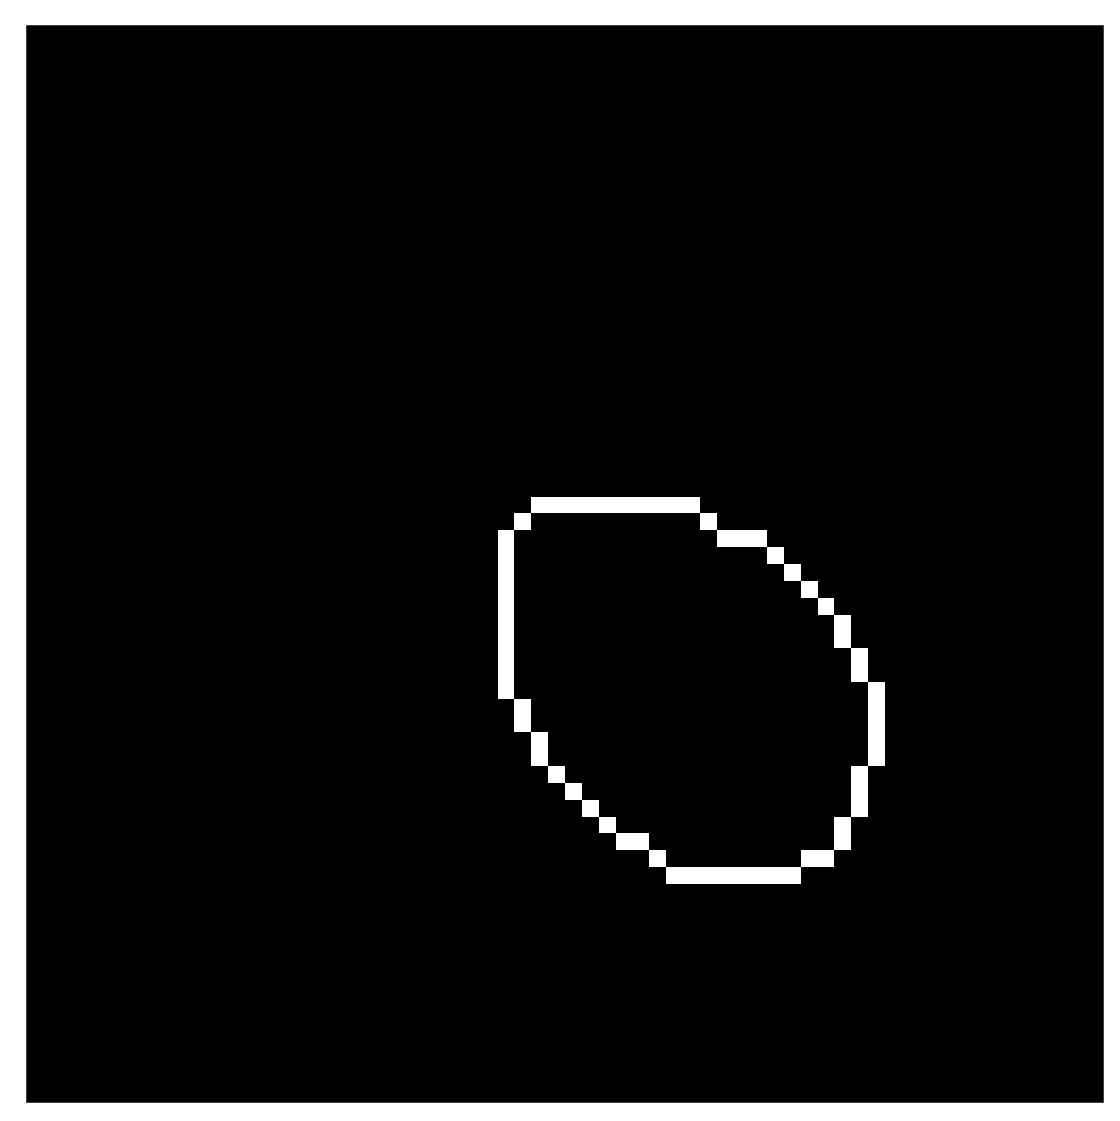

We compute the aforementioned boundary estimate in several steps, including the application of two distinct convolutional neural networks. (a) The first neural network learns to extract the known part of the wavefront set by transforming morphologically opened complex wavelet coefficients to a binary form. (b) The second neural network learns to predict the complete wavefront set from the incomplete wavefront set that has been morphologically dilated. We will discuss the second network, among with the operations related to it, in Section 4.

The training of the neural network uses the morphologically opened complex wavelet coefficients and . After the network performs the thresholding, it outputs a binary mask with ones indicating the location of the wavefront set. See Figure 8(c) for an example result.

See Figure 13(c) for an example output.

See Figure 15(a) for the full singular support.

Then, we can compute the boundary estimate of the singular support using the morphological skeleton operation described in equation (23) of section 2.4. See Figure 15(b). Finally, this learned boundary estimate can be used as an overlay for the PDFP reconstruction. See section 5 for final results.